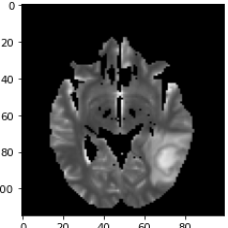

As a first example, we consider a neuroradiological application, where we aim for dividing MRI images showing an abscess into the regions healthy, abscess and edema. The left column in Fig. 6 shows three channels of an MRI dataset using diffusion weighted imaging (DWI), apparent diffusion coefficient (ADC), and T2 sequence. As preprocessing, the ADC maps and T2 images were windowed and standardized to have intensity values between . The second column shows the segmentations obtained by MMCV. Here we chose a weighted linear combination of the three images as the input image. This strategy was found to provide better results than treating the three images as separate channels. We selected the regularization parameter empirically so that it led to the best results. The remaining columns of Fig. 6 show the segmentation masks corresponding to four different regularization parameters. Smaller values of result in quite inaccurate results containing many false positives. The results in the last row, which were obtained by setting the regularization parameter to , show an improvement compared to the ones in the previous columns. Quantitative evaluation metrics are summarized in Table 3.